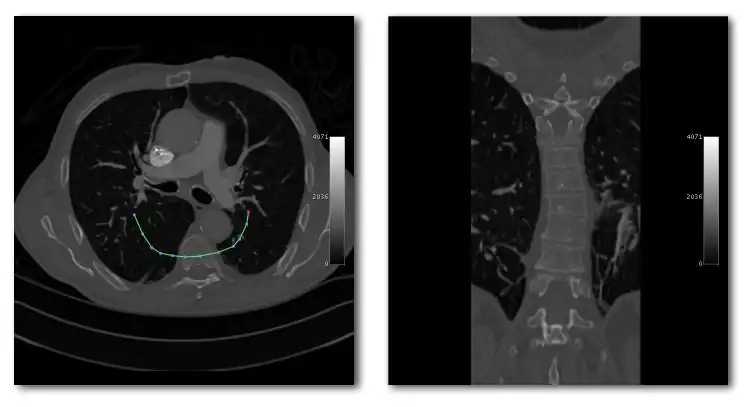

- Curved MPRs can be used for the reconstruction of more complex perspectives, as illustrated in the next figure:

- Here a curve (highlighted in green) can been positioned in the axial images (left panel) to define a curved surface which extends through the voxel data in the z-direction, and voxels from this data can be reconstructed into a two-dimensional image (right panel). Note that more complex curves than the one illustrated can be generated so that, for instance, the three-dimensional course of a major blood vessel can be isolated, or CT head scans can be planarized for orthodontic applications.